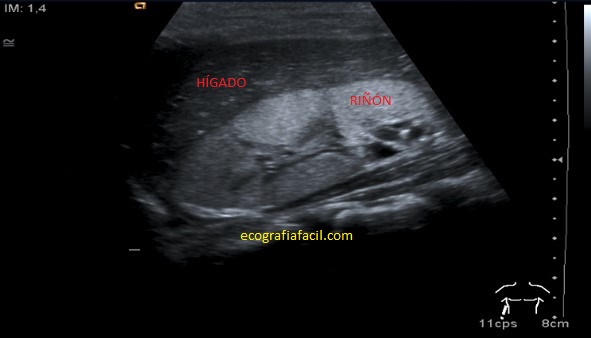

Pielonefritis:

Hallazgos ecográficos:

• Aumento del riñón.

• Alteración de la ecogenicidad, normalmente más hiperecogénico con respecto al hígado, focal o globalmente.

• Compresión del seno renal.

• Masa o masas mal definidas.

Afectación global de la estructura.

Afectación parcial.